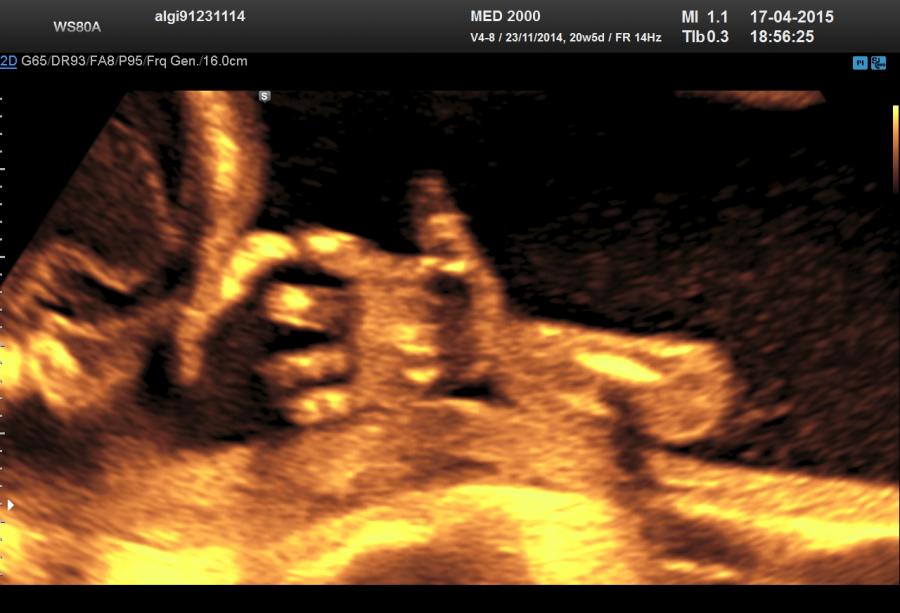

Un altro dato da valutare è il grado di curvatura ossea; le due principali condizioni che possono presentare in epoca prenatale un incurvamento delle ossa lunghe sono l'osteogenesi imperfetta e la displasia tanatofora tipo I (femori a cornetta di telefono).

Per quanto riguarda il rachide la Platispondilia (comunque non facilmente evidenziabile ecograficamente) è presente nella Displasia Tanatofora e nella Displasia Metatropica. Nell'Acondrogenesi tipo I si ha scarsa ossificazione dei corpi vertebrali e costantemente non si visualizza il sacro.

Macrocefalia/Macrocrania è presente nella Acondroplasia, nella Displasia Tanatofora ( il tipo II è caratterizzato da “cranio a trifoglio” ), nell'Acondrogenesi. L'idrocefalia può essere una complicazione dell'Acondroplasia, dell'Osteogenesi Imperfetta e della Displasia Metatropica. Un cranio di consistenza molle (ossa wormiane) è sintomo costante di Osteogenesi Imperfetta anche se può essere presente in altre condizioni quali l'ipofosfatasia, la displasia cleido-cranica, etc. Nell'Ipofosfatasia vi può essere una aumentata ecogenicità della falce cerebrale.